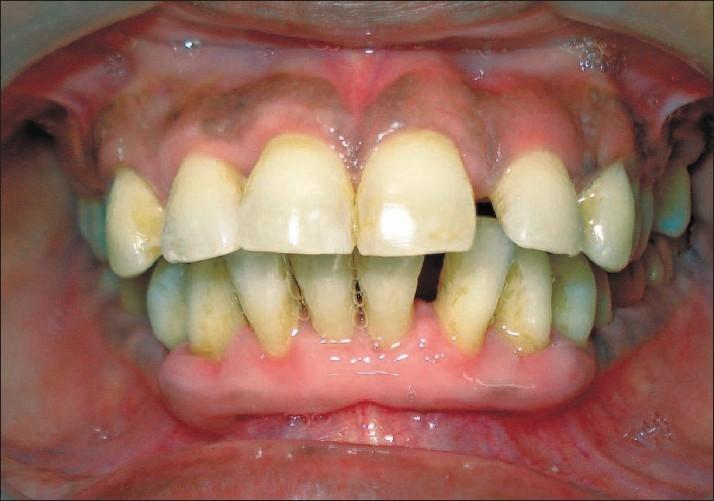

Gingival enlargement is a well recognized unwanted effect associated mainly with anticonvulsant drugs, immunosuppressant drugs and calcium channel blockers. Amlodipine influenced gingival enlargement is comparatively less prevalent amongst calcium channel blockers. It causes aesthetic disfigurement, speech disturbances, abnormal tooth movement and difficulty in mastication. The management of drug influenced gingival enlargement is a challenge for the periodontist, mainly due to less understanding of its pathogenesis, difficulties in selection of proper line of management and recurrence of the enlargement. This report discusses the importance of conservative approach (scaling and root planning along with drug replacement) in the management of a case of amlodipine influenced gingival enlargement. The need for extensive surgery was decreased after this approach.

牙龈增生是一种公认的不良影响,主要与抗惊厥药物、免疫抑制药物和钙通道阻滞剂有关。在钙通道阻滞剂中,氨氯地平引起的牙龈增生相对较少见。它会导致美观受损、言语障碍、牙齿异常移动和咀嚼困难。药物性牙龈增生的治疗对牙周病医生来说是一项挑战,主要是因为对其发病机制了解较少,难以选择合适的治疗方法以及增生复发。本报告讨论了保守治疗方法(刮治和根面平整以及药物替代)在治疗一例氨氯地平引起的牙龈增生中的重要性。采用这种方法后,减少了进行广泛手术的必要性。